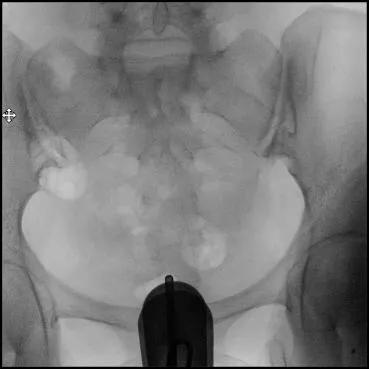

7.摄定位片确定盆腔及导管位置;

定位片